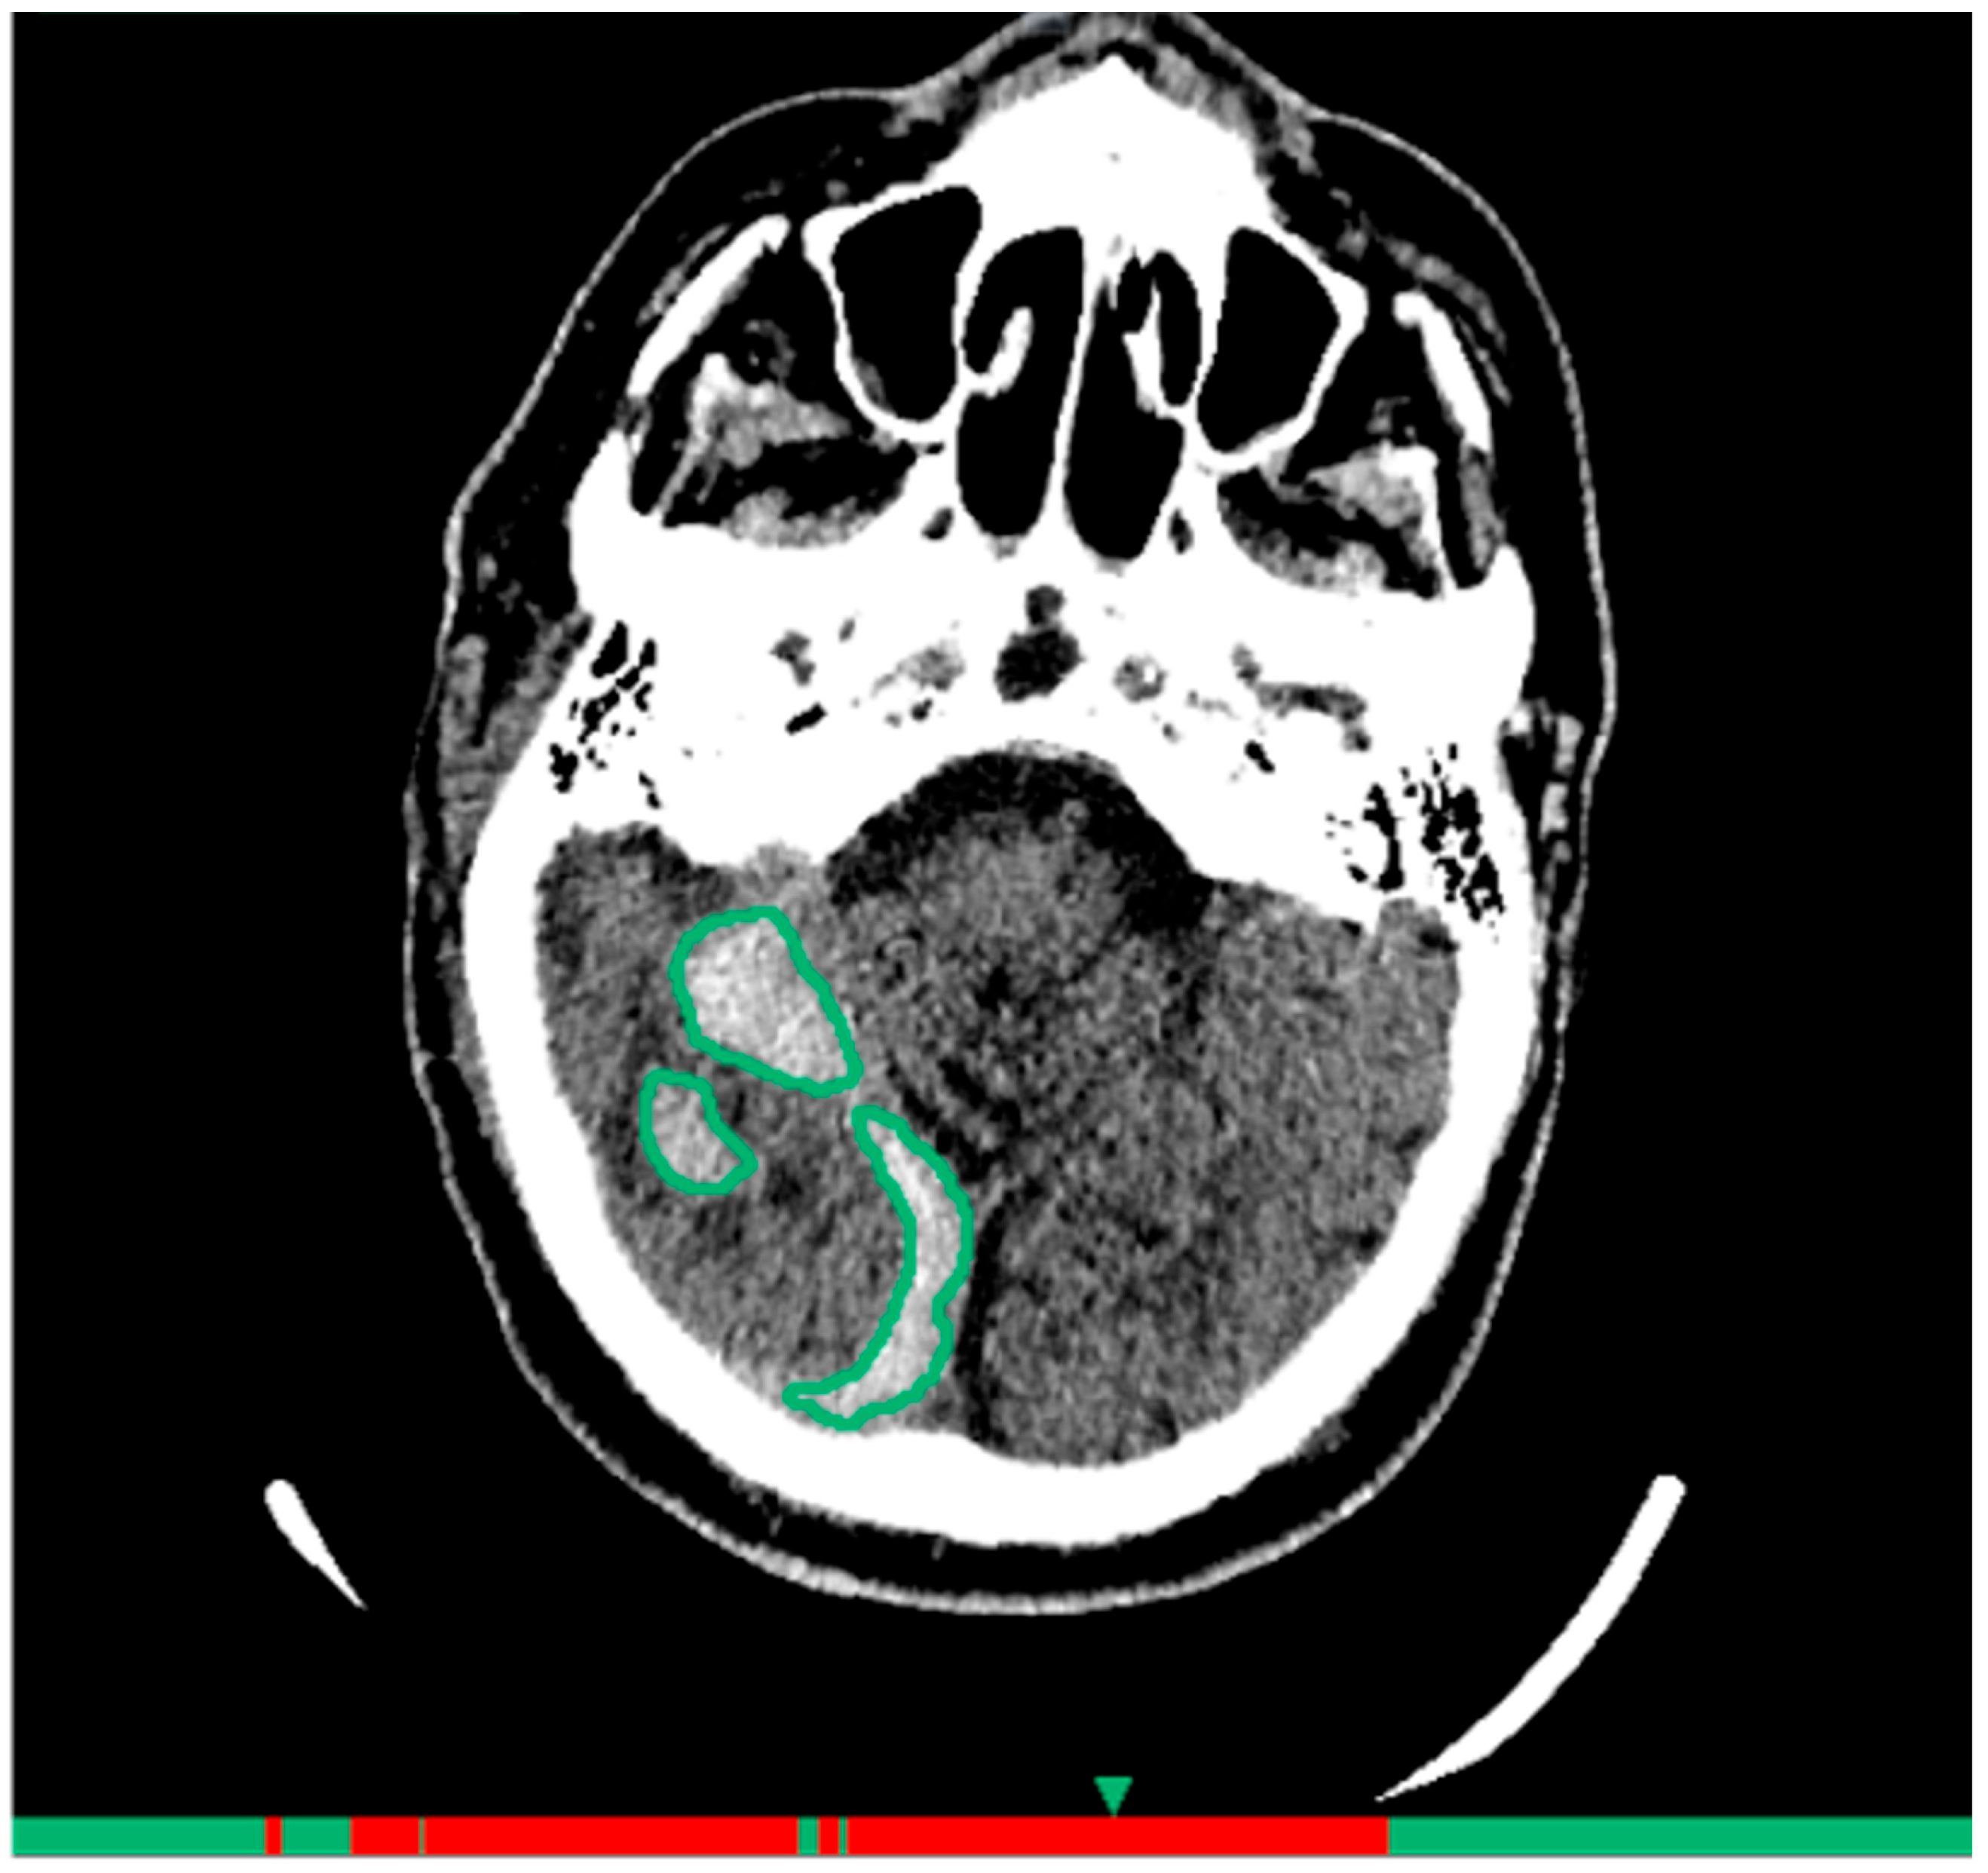

- Complete correspondence: accurate pathological zone localization;

- Partially correct assessment: correct detection with inaccurate localization (e.g., part of hemorrhage not marked);

- False-positive result: AI contoured a structure as pathology not confirmed by expert;

- False-negative result: AI did not contour pathology confirmed by expert.